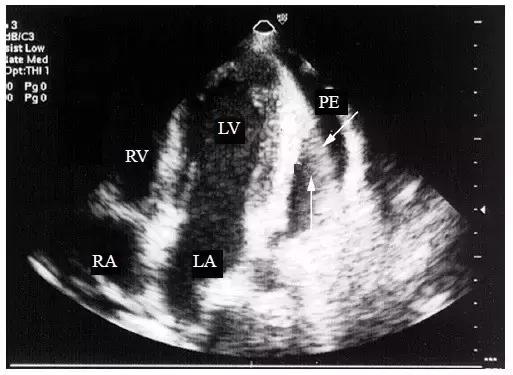

3.将探头置于心尖部,可见暗区中出现带状强回声,即“荡击波”征(图4),若液体以渗出为主,则在液体暗区内出现有规律摆动的带状回声,形如水草或飘带(图5)。

图4 大量心包积液时的“荡击波征”

将探头置于心尖部,大量心包积液暗区中出现带状强回声,即“荡击波”征(箭头所指)

图5 大量心包积液的飘带征

若液体以渗出为主,则在液体暗区内出现有规律摆动的带状回声(箭头所指)